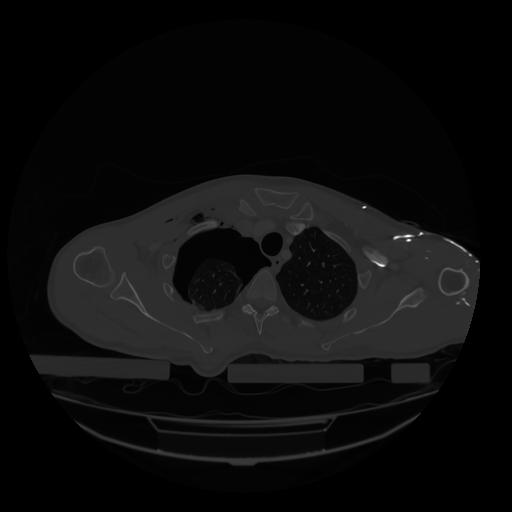

28 CUERPO,CE,Vol,2.0,CUERPO,,